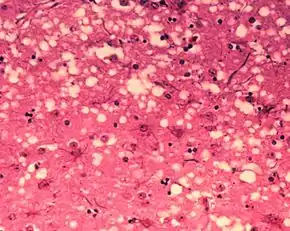

The traditional method of diagnosis relies on histopathological examination of the medulla oblongata of the brain, and other tissues, post mortem. Immunohistochemistry can be used to demonstrate prion protein accumulation.[25]